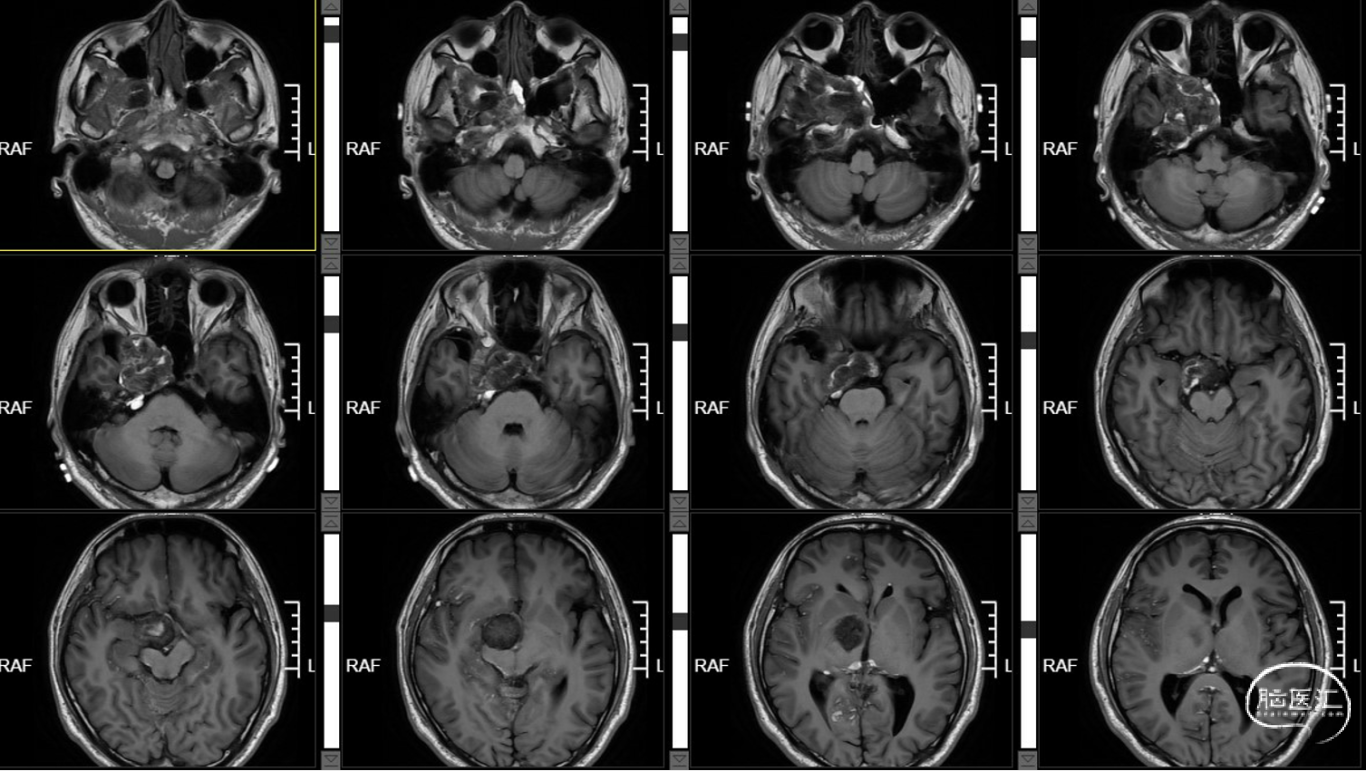

术前T1+C